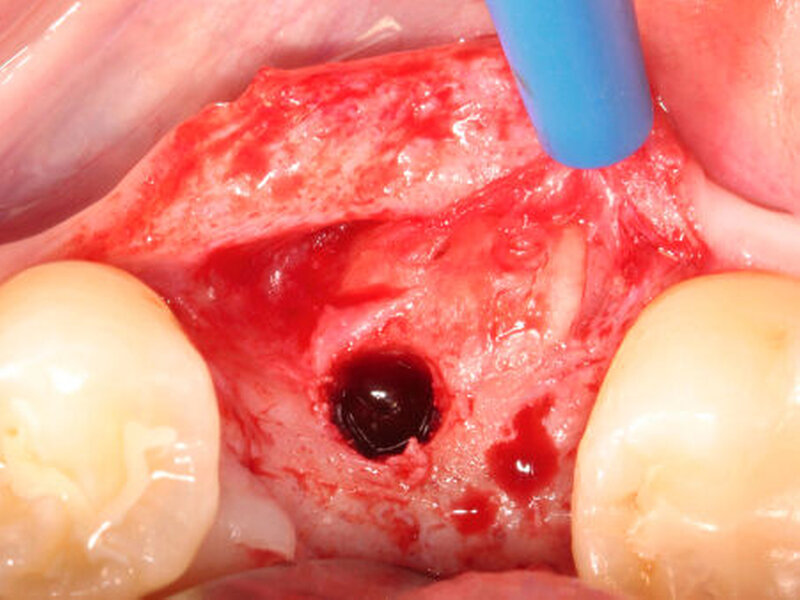

In einem ersten Pilotversuch beim Menschen konnte das Verfahren der autogenen Wurzeltransposition erfolgreich bestätigt werden. Hierbei diente ein retinierter oberer Weisheitszahn als Quelle für das Wurzelaugmentat, das zur lateralen Augmentation einer Schaltlücke im Unterkiefer analog zu dem oben genannten chirurgischen Verfahren eingesetzt wurde. Nach einer Heilungsphase von sechs Monaten zeigten sich deutlich klinische Anzeichen für eine nahezu vollständige Ersatzresorption der Zahnwurzel durch eine mineralisierte Hartsubstanz. Die horizontale Verbreiterung des ehemaligen Defektbereichs ermöglichte eine prothetisch orientierte, regelrechte Implantatinsertion (Abbildungen 5a und b).

Neben retinierten, impaktierten, verlagerten oder überzähligen Zähnen werden im nächsten Schritt auch endodontisch behandelte Zähne ohne Anzeichen einer lokalen Pathologie für die Gewinnung von Zahnwurzelaugmentaten klinisch untersucht (Abbildungen 6a und b).

Neben einer Transposition in bereits bestehende Defektbereiche könnte die Zahnwurzel auch zur direkten Augmentation defizitärer Extraktionsalveolen (zum Beispiel Schalentechnik bei Dehiszenzdefekten) Verwendung finden (Abbildung 6c).